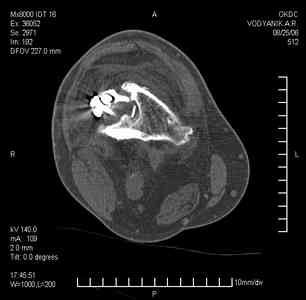

Тугой ложный сустав правого бедра в сочетании неправильно сросшимся переломом большеберцовой кости |

Уважаемые коллеги,В ортопедическое отделение обратился пациент: мужчина 47 лет, который в течение 4-х лет дваждыполучил травму костей, образующих правый коленный сустав. В 2002 v внутрисуставной оскольчатыйперелом проксимального метаэпифиза правой большеберцовой кости; в 2005 v внутрисуставнойоскольчатый перелом дистального метаэпифиза правой бедренной кости. В обоих случаях в разных лечебных учреждениях проводилось оперативное лечение переломов.При осмотре в отделении на основании результатов клинического осмотра и данных визуальныхметодов обследования поставлен диагноз:тугой ложный сустав дистальной трети правой бедренной кости, состояние после накостногоостеосинтеза перелома типа 33-В2.2 ; несросшийся перелом надколенника; неправильно сросшийсяперелом латерального мыщелка правой большеберцовой кости, состояние после металлоостеосинтезаперелома 41-В2.2; сочетанная осевая деформация правой ноги: варусная деформация правого бедра,вальгусная деформация правой голени; посттравматический артроз коленного сустава 4 ст по Kellgren-Lowrence; выраженное нарушение функции ходьбы и опоры. Внешний вид ноги больного, данные рентгенографического обследования и избирательно выделенные компьютерные томограммы приведены в приложении. В именах КТ использовано кодирование уровня по АО, т.е. _41, например, означает проксимальную треть голени.В отделении намечен v очень предварительно v следующий план лечения: 1. Иметь ввиду перспективу тотального эндопротезирования коленного сустава. 2. С учетом п.1 при проведении действий, направленных на устранение ложного сустава бедренной кости не использовать материалы, не подвергающиеся трансформации. 3. В ходе операции, направленной на устранение ложного сустава: А. удалить все металлоконструкции; Б. ревизовать зону пролежня под пластиной на бедре, при наличии признаков достаточной жизнеспособности кости выполнить остеопериостальную декортикацию, дрилинг ложа пластины; В. Удалить рубцовую ткань по плоскости ложного сустава, и в пространстве между костными форагментами, насечь обращенные друг к другу поверхности. Ввести штифт с блокированием (например Stryker с учетом особенностей расположения дистальных блокирующих винтов у этойконструкции). Осуществить остеосинтез с учтанением варусной деформации бедренной кости. Пространство в зоне ложного сустава и пустоты в метафизе бедренной кости заполнить резорбирующимся цементом на основе гидроксиапатита кальция. Для дистальной фиксации использовать винты с переменным шагом резьбы. Вариант:, винты вводить после заполнения метафиза цементом. Дополнительные виды создания межфрагментарной компрессии во встречно-боковом направлении обсуждаются. Г. Быть готовым к кровопотере. Д. Учесть высокий риск инфекции, тромбоэмболических осложнений. Е. Вопрос о внешней иммобилизации решить по результатам оценки стабильности остеосинтеза. Вариант - одноосевой стержневой аппарат для шунтирования гвоздя с модулем на голени и дистракцией коленного сустава в течение 3-5 недель. Просим вашей критики намеченного плана и конструктивных предложений. С уважением к сообществу, Ординатор В.С. Саплин

Движения приличные, есть за что бороться. Такая ротация голени кнаружи, если она действительно есть (для уточнения можно сделать КТ на уровне обоих метафизов и бедреных, и берцовых ксотей, не меняя положение ног во время съемки), большого значения не имеет. А уж на фоне всего остального тут - вообще говорить не о чем.